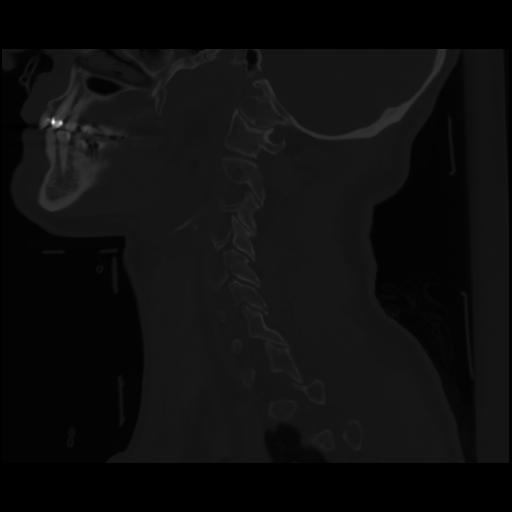

14 P.BLANDAS,,Sagittal,2.000,P.BLANDAS,Sagittal,